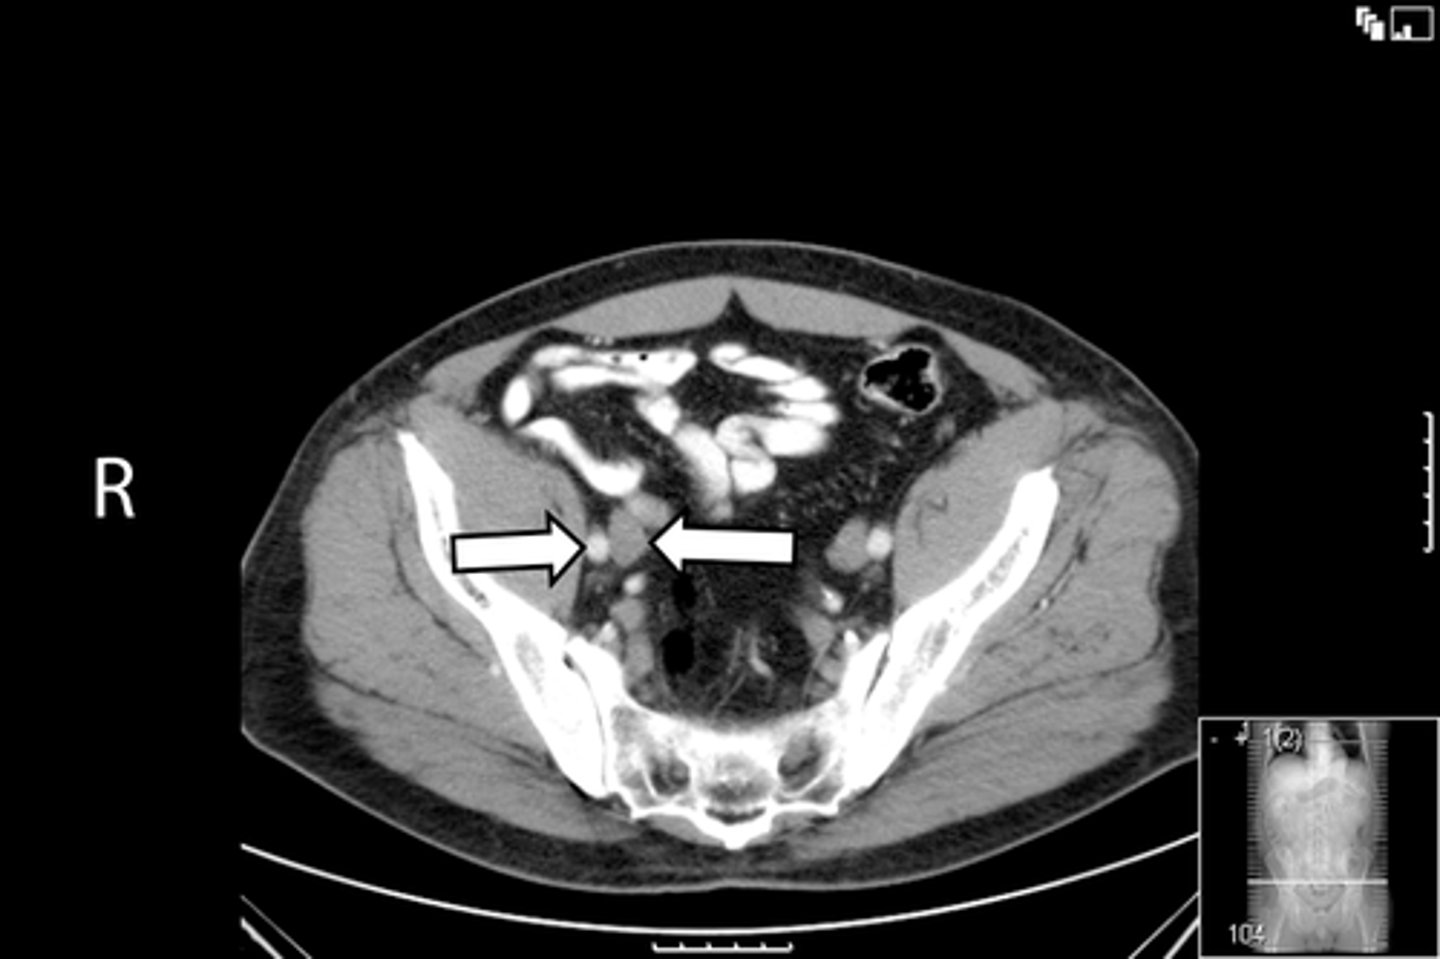

<p>What is indicated in the image?</p>

Axial male pelvis CT

What is the image?

<p>What is the image?</p>

Descending colon

L common iliac artery

L gluteus muscle

L iliacus muscle

L ilium

L psoas muscle

R common iliac artery

R gluteus muscle

R iliacus muscle

R ilium

R psoas muscle

R and L rectus abdominis